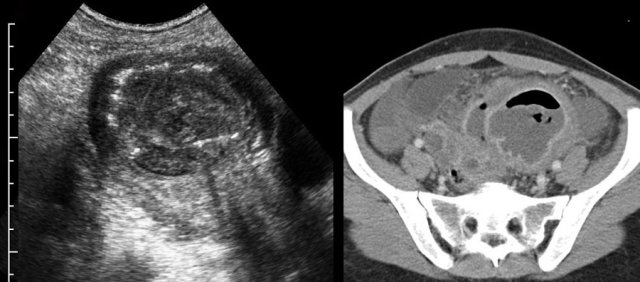

TOA case 4 (infected endometriotic cysts)

These images are of a 29-year old woman, suspected for appendicitis. CRP 185, WBC 17.

US shows a normal compressible appendix, thereby excluding appendicitis.

Large, thick-walled, septated cystic structures, filled with debris-like material, were found on both sides of the uterus (ut.), touching each other posteriorly (“kissing ovaries”).

This is somewhat suspect for bilateral infected endometrotic cysts.

The patient was treated with antibiotics and laparoscopic drainage.

There was a protracted course, but eventually regression of the abnormalities.

An MRI six months later, demonstrated all the signs of deep infiltrating endometriosis, also invading the rectum, thereby confirming the diagnosis of endometriosis.